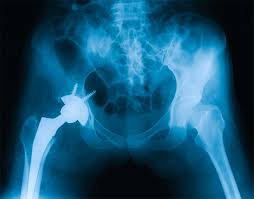

Dubla Artroplastie Totala De Sold Realizata Cu Succes In Spitalul Euroclinic Reginamaria Ro

vizitati articolul complet aici : https://www.reginamaria.ro/articole-medicale/dubla-artroplastie-totala-de-sold-realizata-cu-succes-spitalul-euroclinic

Artroplastia de sold (proteza de sold) este o urgenta? B) artroplastia totala de sold sau proteza totala de sold cu cele 2 mari variante: Citeste acum toate articole despre protezare totala de sold pe digi24.ro.

Însă, artroplastii totale de şold au fost efectuate cu succes la pacienţi de toate vârstele, de la adolescenţi cu artrită juvenilă până la pacienţi în vârstă, cu artroză. Procedura e cel mai larg folosita in tratamentul coxartrozei, cu scopul de a ameliora durerea, de a reda mobilitatea articulara si de a. Aduce din avantajele unei proteze necimentate acelor pacienti la care o proteza necimentata nu are o indicatie ferma.

Sunt fixate la os cu ajutorul cimentului ortopedic. Am si eu o problema, am 35 de ani iar in 2001 mi sa pus o proteza totala de sold, iar prin 2003 mi sa infectat. O inlocuire totala de sold reprezinta o procedura chirurgicala prin care cartilajul si oasele afectate ale soldului sunt inlocuite cu un material artificial.